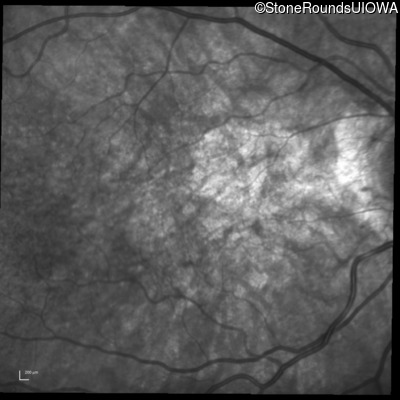

Infrared Fundus Photograph - Left - 20/160

Exemplar